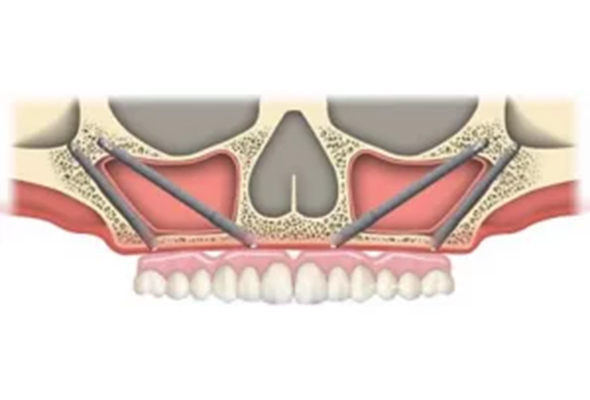

Zygomatic Dental Implants are a unique type of dental implants used for patients with severe bone loss in the upper jaw, especially in the posterior region. Named after the zygoma (cheekbone) where they are anchored, these implants are longer than conventional dental implants, often ranging from 30-50 millimeters in length.

The Zygomatic implant procedure involves placing the implants in the dense zygomatic bone, which provides robust support for the prosthetic teeth. This allows for a secure and stable full-arch restoration, even in patients with significant bone loss where traditional implants may not be viable.

Like Pterygoid implants, Zygomatic implants also eliminate the need for bone grafting or sinus lift procedures, reducing the complexity and duration of the treatment. They offer immediate functionality, allowing patients to enjoy a fully functional set of teeth promptly after surgery. While the procedure requires a high level of expertise, when performed correctly, Zygomatic implants provide a highly successful and long-term solution for full-mouth rehabilitation.

Pterygoid implants are placed in the pterygoid plates of the sphenoid bone at the back of the upper jaw, while Zygomatic implants are anchored in the zygoma (cheekbone).

Zygomatic implants are typically longer than Pterygoid implants. They can range from 30-50 millimeters, while Pterygoid implants typically measure between 15 to 20 millimeters.

Placement of Zygomatic implants generally requires a higher level of surgical expertise due to their proximity to critical anatomical structures, such as the eye socket and the maxillary sinus.

While both can be used for patients with severe bone loss, Zygomatic implants are typically reserved for more extreme cases where even Pterygoid implants may not be viable.